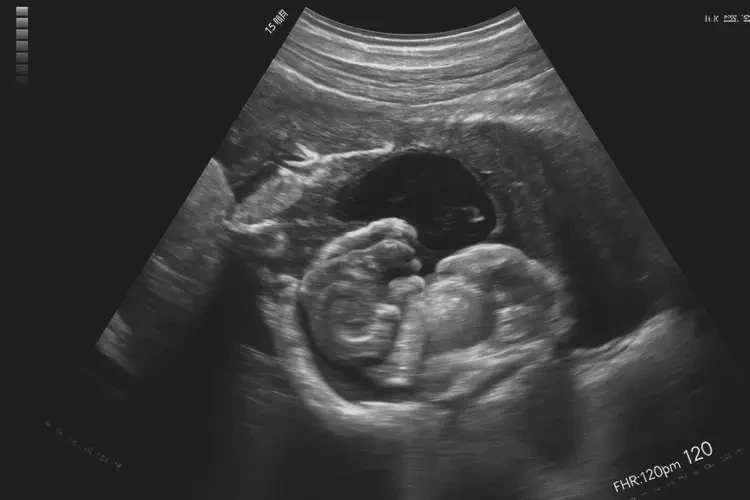

120次/分钟

怀孕第15周胎心在120次/分钟是正常的。胎心率是指胎儿心脏每分钟跳动的次数,是评估胎儿健康状况的重要指标之一。在怀孕的不同阶段,胎心率会有所变化,但通常在一定的范围内波动。

- 孕中期(12-28周):胎心率逐渐稳定,通常在120-160次/分钟之间。